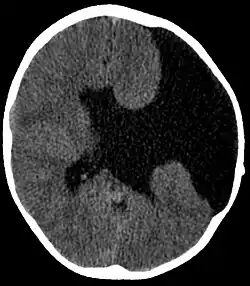

Unter dem Begriff Schizenzephalie wird eine seltene kortikale Fehlbildung des Gehirns auf der Grundlage einer Homöobox-Genmutation (EMX2) verstanden. Sie wird zur Gruppe der Fehlbildungen des Zentralnervensystems gezählt.

Als Ursache konnte nachgewiesen werden, dass es zu einem Ausfall eines für die Proliferation der Vorstufe der Neuronen im Bereich der Hirnrinde zuständigen Transkriptionsfaktors gekommen ist. Dadurch entstehen bereits in der pränatalen (vorgeburtlichen) Entwicklung des Kindes Spaltbildungen unterschiedlicher Grade zwischen den beiden Großhirnhälften (Hirnhemisphären). Liegen diese Fehlbildungen bilateral (beidseitig) vor, kann es zu einer Verbindung (Kommunikation) zwischen Hirnventrikeln kommen.